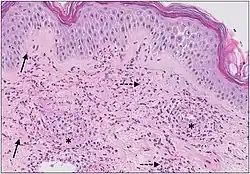

Micrograph of cutaneous small-vessel vasculitis. The section shows all features of leucocytoclastic vasculitis. A mixed inflammatory cell population surrounds the postcapillary venules of the superficial dermis. The infiltrate consists of neutrophils with nuclear dust (dashed arrows) and shows high affinity for the vessels. Features of vascular injury are shown, including fibrinoid necrosis (asterisks) and erythrocyte extravasation (solid arrows).[11]